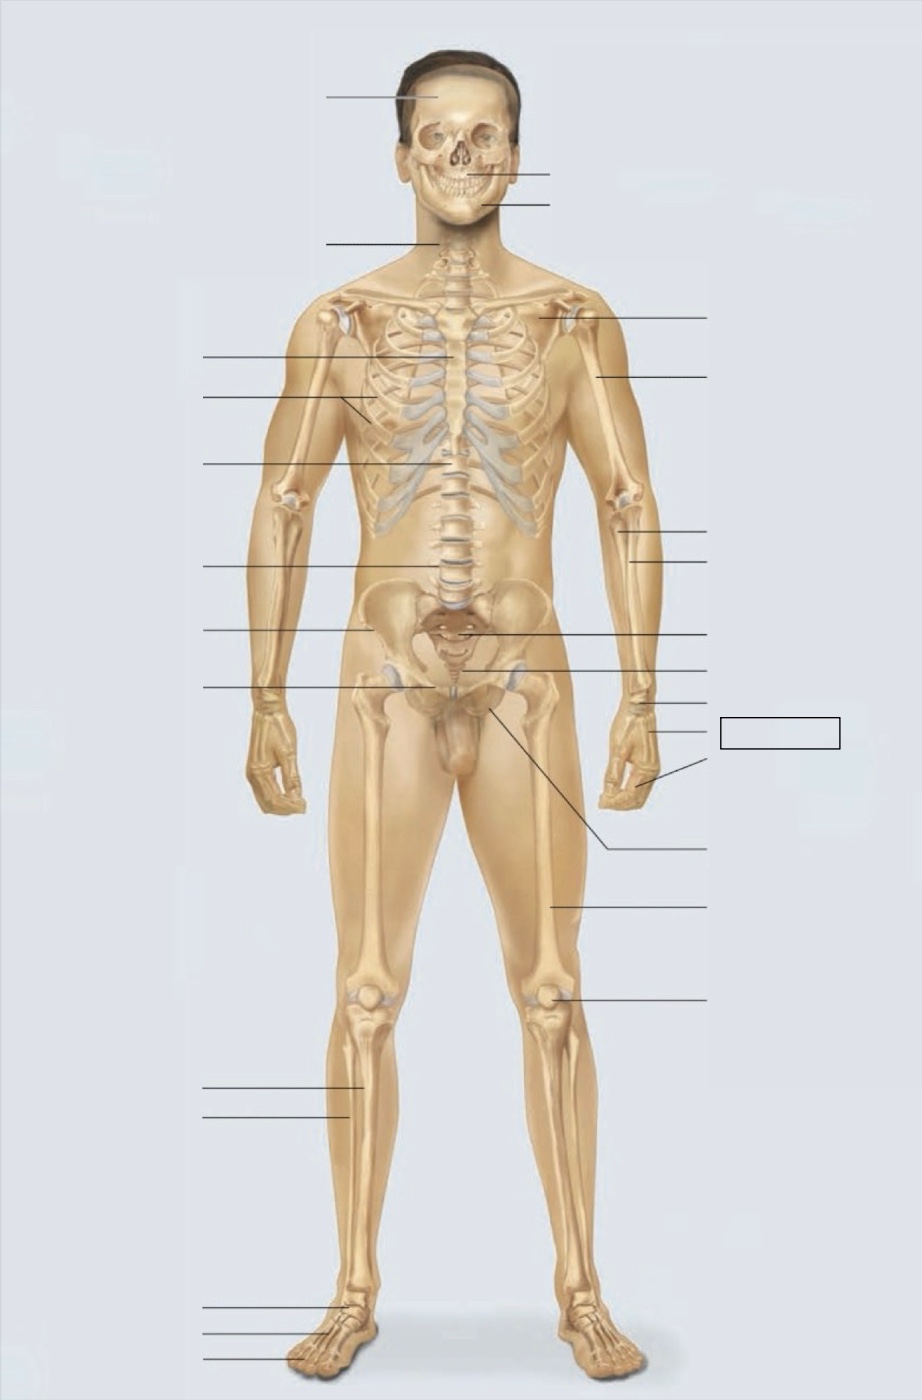

maxilla

mandible

scapula

humerus

ulna

radius

sacrum

coccyx

carpals

metacarpals

phalanges

ischium

femur

patella

phalanges

metatarsals

tarsals

fibula

tibia

pubis

ilium

lumbar vertebrae (L4)

thoracic vertebrae (T11)

ribs

sternum

cervical vertebrae

skull